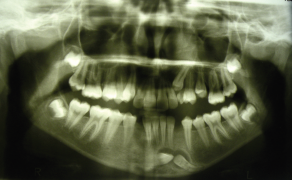

Streszczenie: W pracy przedstawiono postępowanie kliniczne u pacjentki z obustronnym wrodzonym brakiem siekaczy żuchwy. Ten stan jest stosunkowo rzadki i zawsze wymaga dokładnego rozpoznania i planowania leczenia. Wybrana dla pacjentki strategia leczenia obejmowała zamknięcie przestrzeni poprzez protrakcję tylnych zębów żuchwy i zastąpienie brakujących siekaczy kłami. Ponadto omówiono problemy wynikające z takiego planu leczenia, takie jak okluzja chroniona przedtrzonowcami i rozbieżność wielkości zębów. W oparciu o przypadek przedstawiony w niniejszej pracy można wnioskować, że zamknięcie przestrzeni można uznać za skuteczne podejście terapeutyczne, pozwalające na uzyskanie zadowalających wyników funkcjonalnych i estetycznych.

Hipodoncja jest definiowana jako wrodzony brak jednego lub kilku zębów [1]. Cięższymi postaciami agenezji zębów są oligodoncja i anodoncja, charakteryzujące się odpowiednio brakiem więcej niż sześciu zębów i całkowitym brakiem zębów. Są one zwykle związane z innymi schorzeniami ogólnoustrojowymi, takimi jak: zespół Downa, dysplazja ektodermalna i zespół Ellisavan Crevelda [1, 2]. Istnieją cztery główne teorie dotyczące etiologii agenezji zębów; może być ona traktowana jako manifestacja trendu ewolucyjnego lub może być spowodowana czynnikami środowiskowymi albo ogólnoustrojowymi, takimi jak: uraz, stan zapalny, zakażenia kości szczęki/żuchwy czy też zaburzenia hormonalne [...]